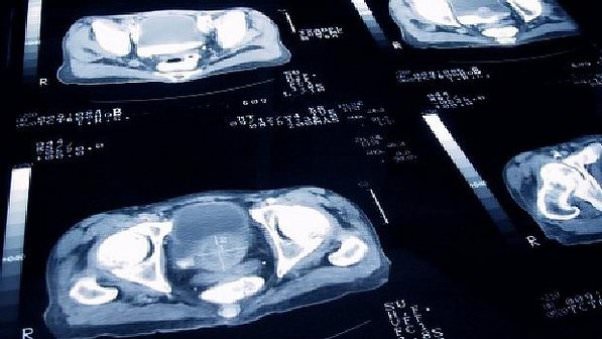

Porém, grande parte dos pacientes ainda adia a ida ao médico, principalmente por causa do receio do exame de toque. De acordo com o urologista Leonardo Lima Borges, no entanto, como o câncer de próstata geralmente não dá sintomas no início, esse exame é extremamente importante para o diagnóstico precoce da doença, junto com o PSA, que é um exame de sangue. No entanto, um resultado alterado no exame de PSA não significa um câncer, como alertou o médico, e pode ser apenas um aumento benigno da próstata.